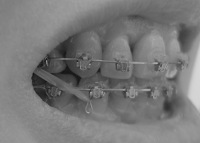

上から。

2008/4/15撮影

2008/5/20撮影

右側の隙間は0.5ミリになりました。

左側は1ミリほどの隙間が2箇所残ってます。